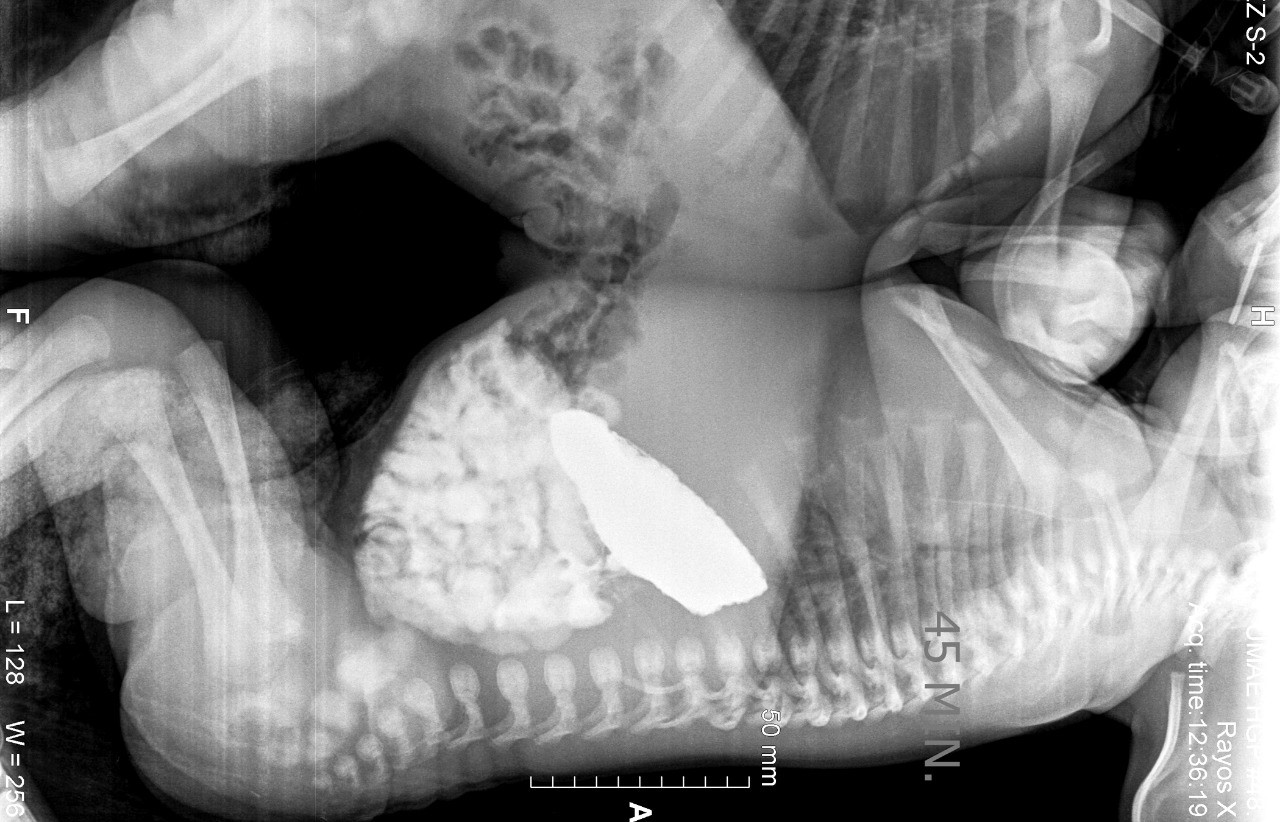

Tras diversos exámenes de tomografía, ecocardiograma y resonancia magnética, cuando los niños cumplieron 41 días de vida, fueron programados para la cirugía que los separaría.

La cesárea se programó para el día 15 de diciembre de 2017; ambos nacieron sin complicaciones, pesaron poco más de cinco kilogramos, con una talla de 45 centímetros.